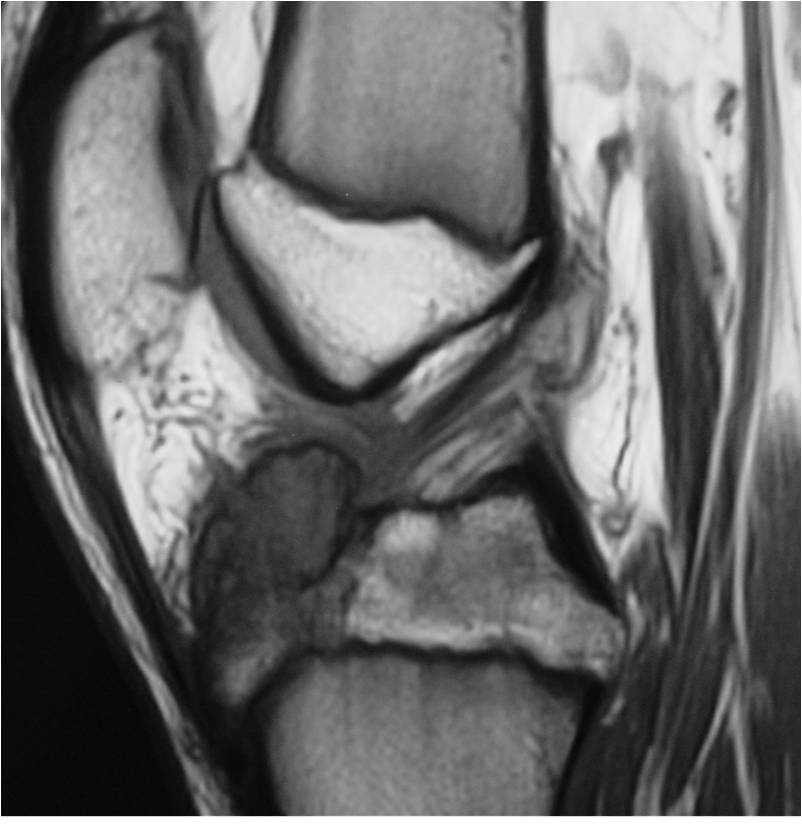

- (MRI appearance)

- Geographic, well circumscribed lesion in the epiphysis

- Intermediate Signal on T1

- High signal on T2 mixed with low signal areas (low signal areas proposed to be secondary to lysosomal content of highly cellular areas)

- Fluid/Fluid levels demonstrated in tumors that have undergone ABC change (aneurysmal bone cyst change)

- Extensive Surrounding edema is common

- Joint effusion in 30-50% of cases